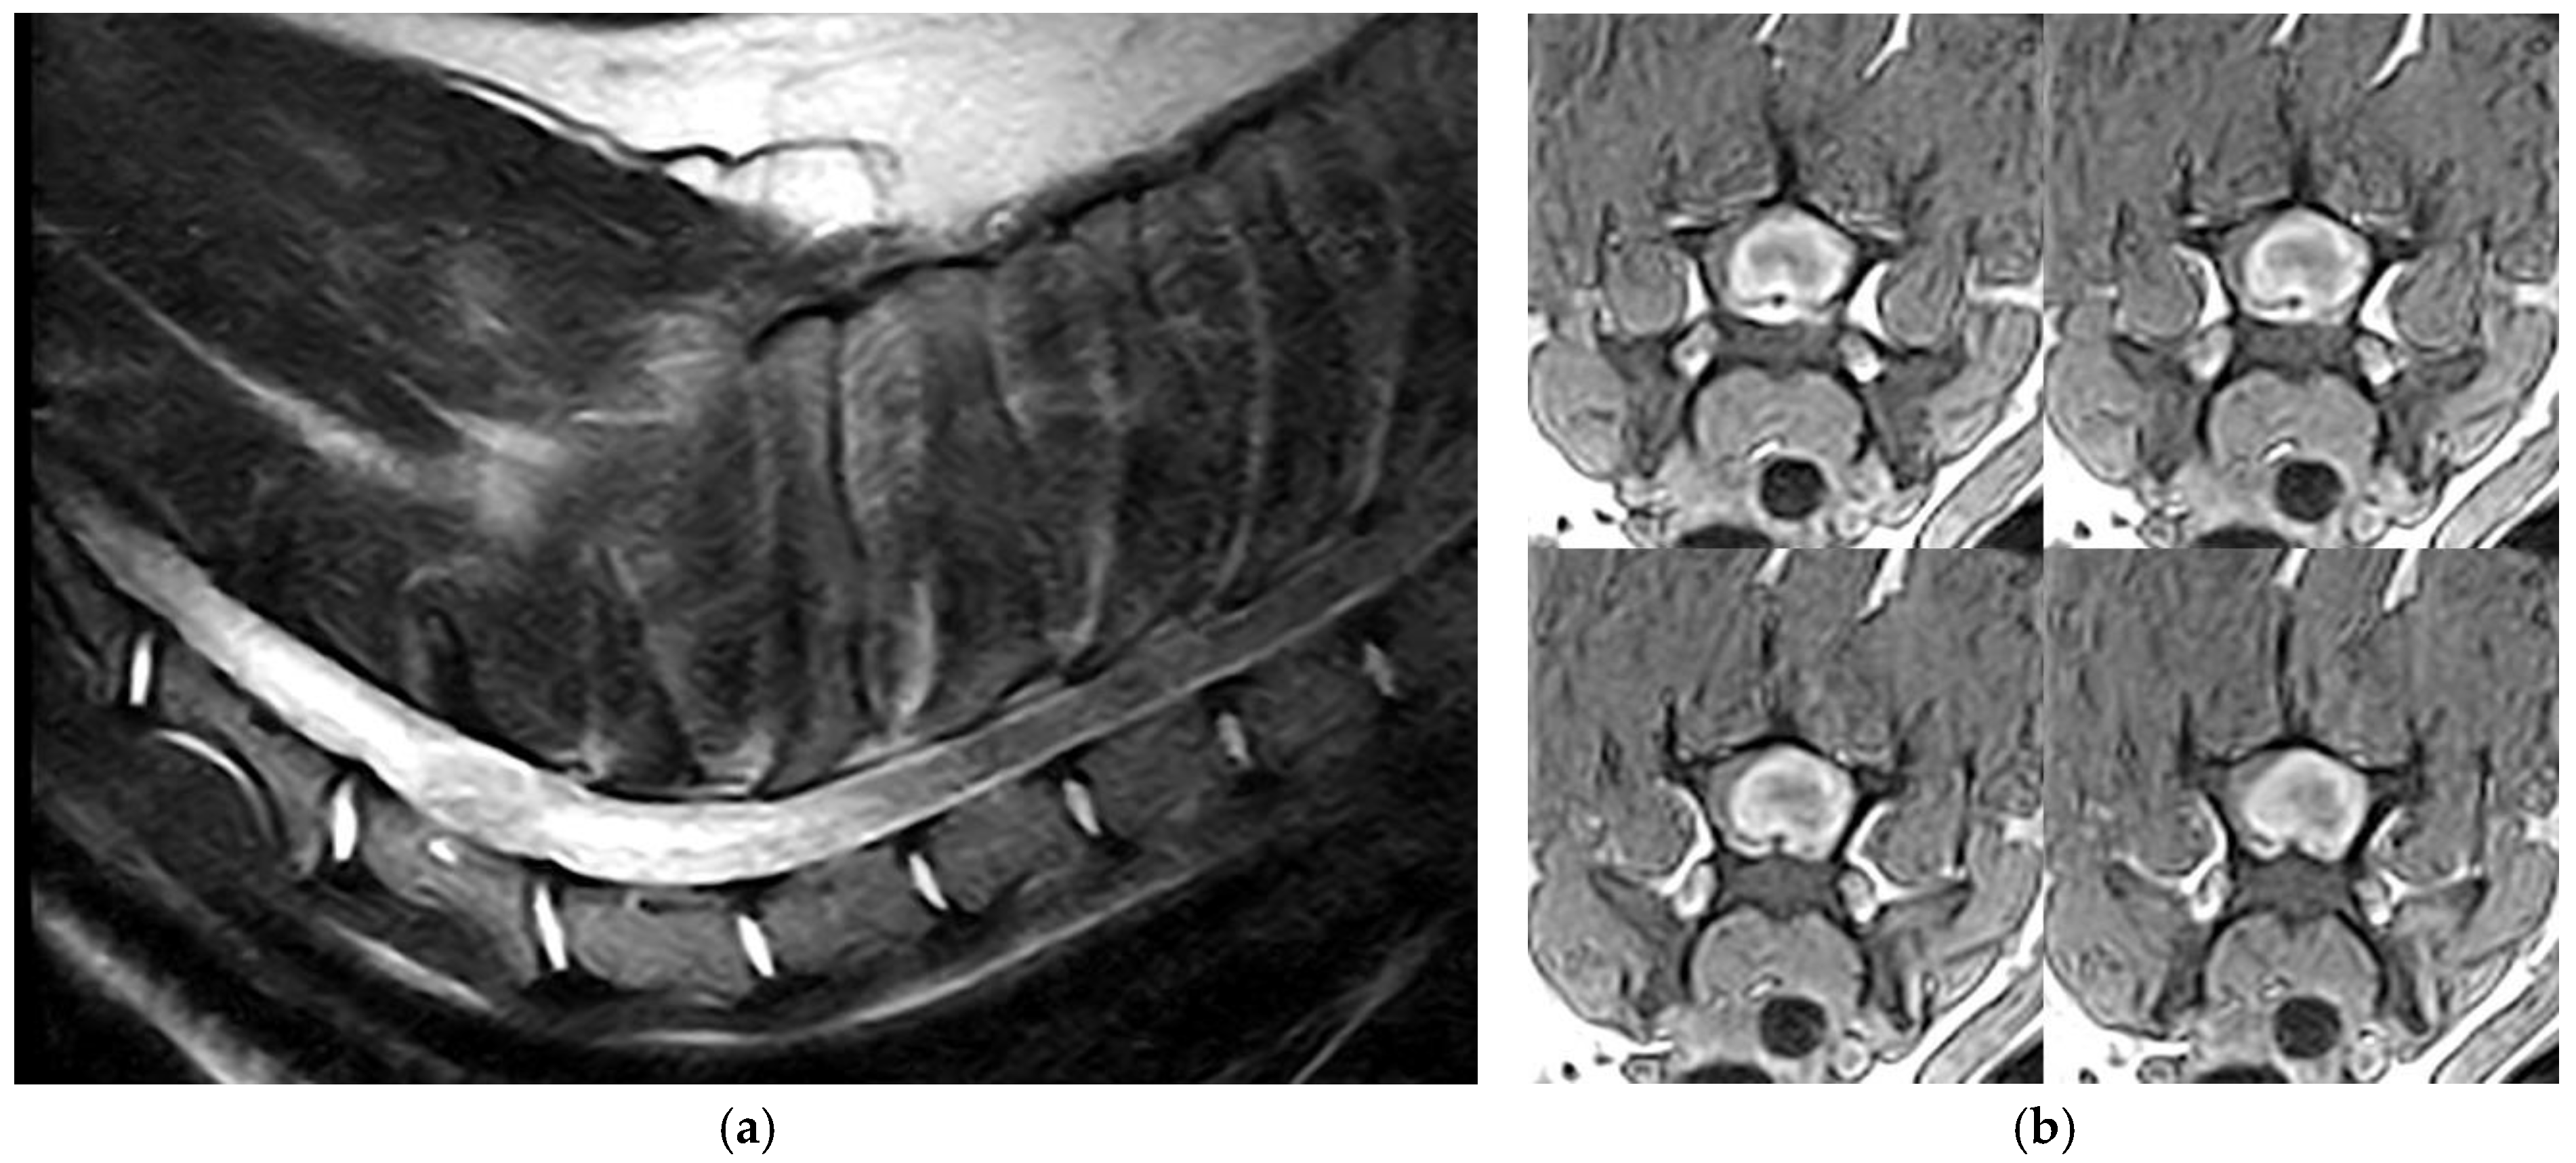

3.1. Clinical and Imaging Findings

3.2. Pathological Findings